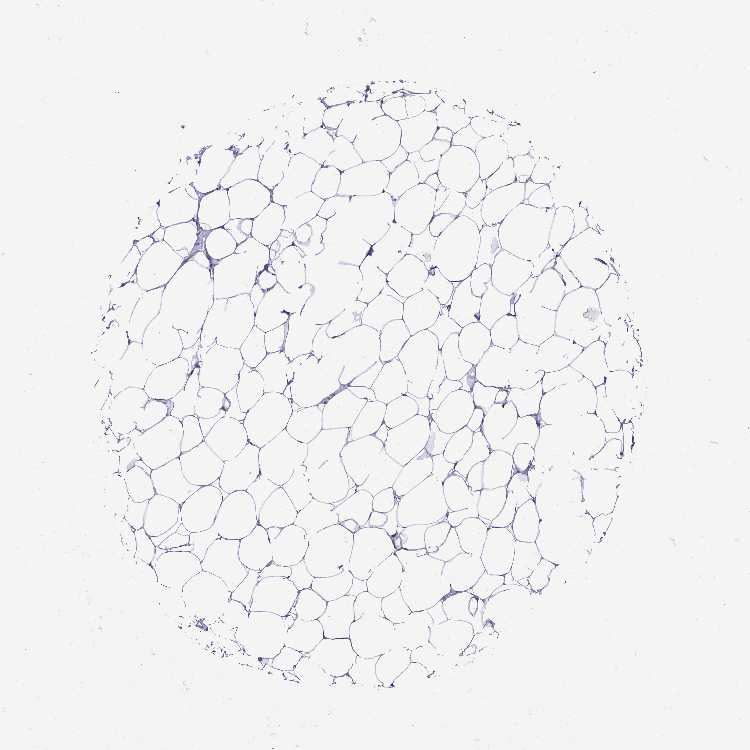

BREAST - Antibody stainingi

Antibody staining in the annotated cell types in the current human tissue is reported as not detected, low, medium, or high, based on conventional immunohistochemistry profiling in selected tissues. This score is based on the combination of the staining intensity and fraction of stained cells.

Each image is clickable and will lead to virtual microscopy that enables deeper exploration of all samples and also displays staining intensity scores, fraction scores and subcellular localization as well as patient and tissue information for each sample.

Antibody HPA027062Antibody CAB010059

Adipocytes Not detectedNot detected

Glandular cells Not detected-

Myoepithelial cells Not detected-